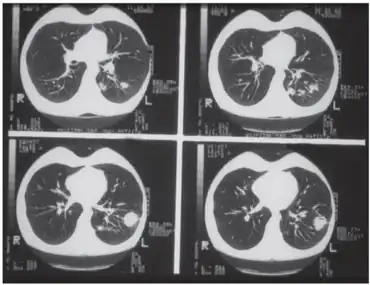

| Pulmonary histoplasmosis in a 29-year-old female | |